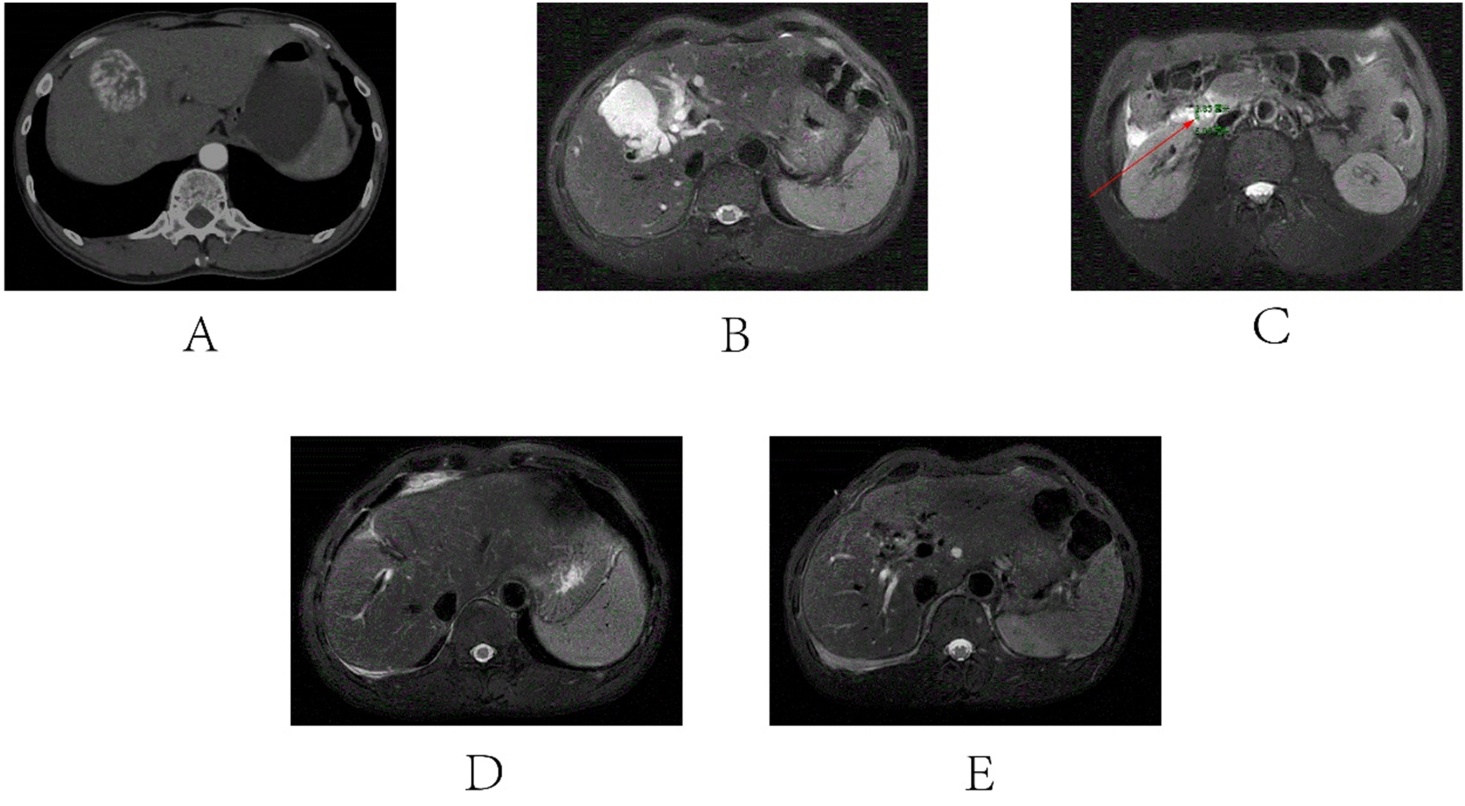

一名51岁的男性患者,因肝血管瘤行肝部分切除术后83天因右上腹疼痛伴皮肤、巩膜黄染加重2天急诊入院,急诊检查发现,右上腹部压痛,全腹部CT发现:肝周积液,肝S8有一类圆形低密度灶,大小约4.7 cm;胆总管下段新形成结石,大小约0.6 * 0.2 cm,胆总管及肝内胆管扩张,胆囊切除术后改变(见图1(A)-(C))。实验室结果检查发现:白细胞计数5.3 × 109/L总胆红素(TBIL) 76.1 µmol/L,结合胆红素(DBIL) 50.1 µmol/L,非结合胆红素26 µmol/L,丙氨酸氨基转移酶(ALT) 240 U/L,天门冬氨酸氨基转移酶(AST) 126 U/L,尿胆原70 µmol/L,胆红素70 µmol/L (见表1)。

注:A:肝部分切除术后复查,手术创面胆管及肝内胆管形态正常,未见扩张,残腔内未见结石影。B:肝切除术后第83天影像,显示残腔与右肝胆管相通,肝内胆管明显扩张,残腔及胆管内可见胆汁淤积。C:肝切除术后第83天影像,胆总管下段可见约0.6 cm × 0.2 cm结石,同时伴肝外胆管扩张。D:经ERCP治疗后1个月复查,残腔及肝内胆管内胆汁淤积明显减少,残腔直径较前显著缩小。E:经ERCP治疗后3个月复查,肝S8血管瘤术后改变,术区未见明显积液,肝内胆管形态正常,未见扩张。

Figure 1. Relevant radiological images of the patient before and after treatment

1. 患者治疗前后相关影像学图像

在获得患者知情同意后,在内镜下行十二指肠乳头肌切开取石 + 内镜逆行胰胆管造影(ERCP) + 短期) (7天)内镜下鼻导管引流术(ENBD),解决胆总管梗阻后,因为患者的肝术后断面残腔内存在积液,于是在超声引导下腹腔穿针置管引流术(PTCD),术后残腔明显缩小,肝内外胆管扩张明显改善,但残腔内胆道漏管仍未闭合,为防止切开取石水肿导致梗阻和支架的机械支撑预防胆管狭窄,于是行ERCP + 内镜下胆管支架置入术,术后引流管引流出胆汁(见图1(D))。患者最终治疗措施是:内镜下行十二指肠乳头肌切开取石 + 短期(7天) ENBD + PTCD + 内镜下胆管支架置入术,考虑瘘道愈合时间久,与患者沟通后,门诊拔管随访。出院后3个月,患者上腹部疼痛明显缓解,影像学提示肝术后断面残腔胆管瘘道愈合良好,行内镜下胆道支架拔除术 + 腹腔引流管拔除术(见图1(E))。拔管后一个月复查,上腹部疼痛症状消失,肝功能恢复正常(见表1)。